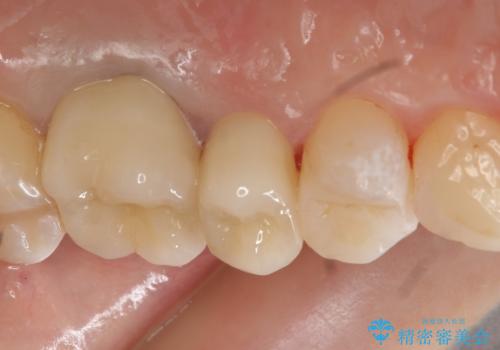

- 左上4、5、6番目の歯を白くしたいといらっしゃった方の症例です。

4番目の歯はセラミックインレーによる修復、5・6番目の歯はオールセラミッククラウンによる補綴を行いました。

今回用いたオールセラミッククラウンはジルコニアフレームという白い素材の上にセラミックを盛っているため、審美性が非常に高いのが特徴です。

また、ジルコニアは人工ダイヤモンドの材料にも使われているほど高い強度を持っており、そのためオールセラミッククラウンは審美性だけでなく、奥歯やブリッジの補綴も可能とするクラウンです。

当院のセラミックインレーはemaxという強度と審美性に優れた材料を使用しています。

またプレス方式でインレーを製作しているため、削り出しで製作するCADCAMより優れた適合性も持ち合わせており、虫歯が再発しにくい修復物です。